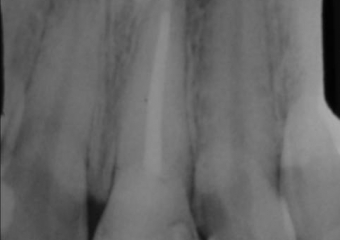

Dente 21 com fratura

Raio X inicial do dente 21 fraturado